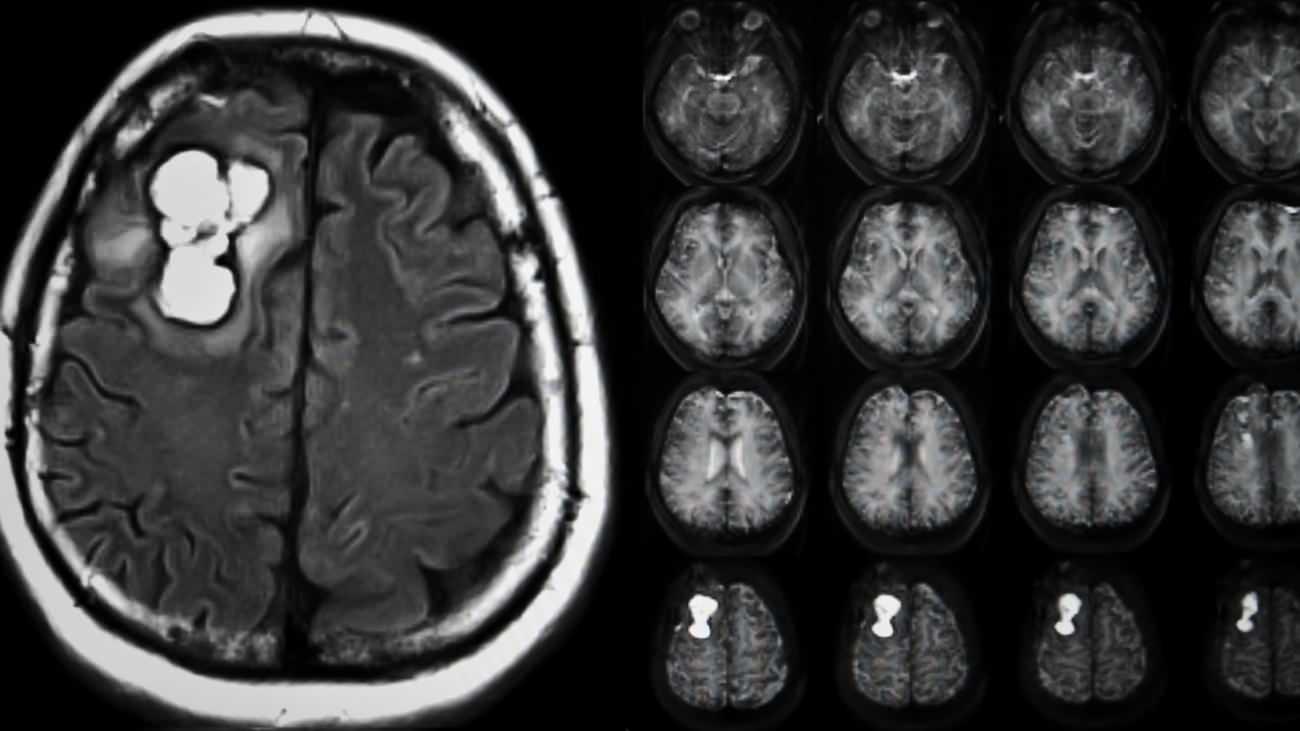

Beyin tümörlerinin kesin tanısı için MR çekiminin altını çizen Dr. Gökçek, “Kapalı alan korkusu olan hastalar için tomografi kısa müddette bilgi verebilir. Fakat beyin tümörlerinin hakikat halde tespiti ve lokalizasyonu için MR şarttır” diye konuştu.